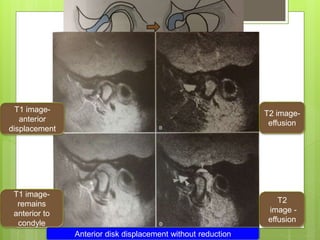

Anterior disk displacement without reduction

T2 image-

effusion

T1 image-

anterior

displacement

remains

anterior to

condyle